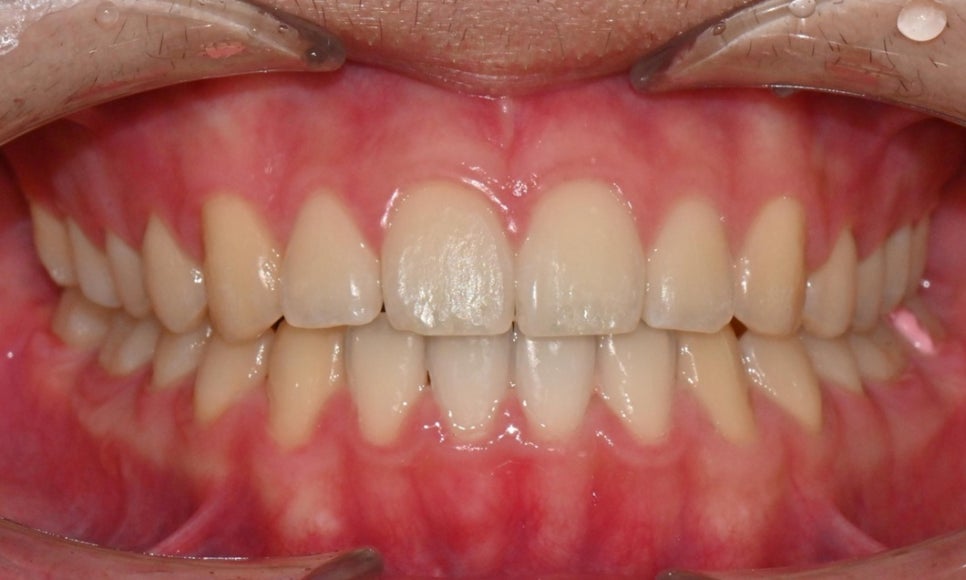

외관상으로는 아랫입술이 돌출되어 보이고 아래 치아가 좌측으로 치우치면서 치아 중심선(midline)이 맞지 않는 상태였습니다. 또한 환자는 어릴 적 넘어지면서 앞니가 깨졌던 외상 병력이 있었고, 그 영향으로 앞니 뿌리가 부분적으로 흡수된 상태였습니다.

2024.12. 초진 구내사진 - 연세정원치과

정밀 검진 결과, 하악 치열이 좌측으로 틀어져 있었고 그로 인해 위아래 치아 중심선이 일치하지 않았습니다. 아래 치열이 전체적으로 전방 위치하여 아래 입술 돌출이 더 도드라져 보이는 상태였습니다. 그리고 상악궁이 하악궁보다 좁아서 앞니 부위 일부 반대로 물리는 치아 교합도 관찰되었습니다. 특히 외상 치아의 경우, 교정력 적용시 추가적인 염증성 치근 흡수 위험이 존재하기 때문에, 치료 중 지속적인 관찰이 필수적인 상황이었습니다.

약 1년 간의 교정 치료를 통해 어긋나 있던 치아 중심선이 자연스럽게 맞춰졌고, 중심선 비대칭이 개선 및 하악 아랫입술 돌출도 눈에 띄게 호전되었습니다. 무엇보다 치료 기간 동안 앞니의 치근 흡수는 추가적인 진행 없이 안정적으로 유지되었습니다.

돌출을 조금 더 개선하는 것을 추천했으나, 환자가 갑자기 군 입대를 하게 되어 현 상태로 치료를 마무리하기로 하였습니다. 치료 전후 치아 위아래 중심선이 일치하며 좌우 어금니 교합도 향상되었습니다. 하악 치열의 후방 이동으로 아래 입술의 돌출도도 많이 개선되었습니다. 멀리서도 믿고 내원해주고, 치료 기간 동안 성실히 협조해준 환자분께 감사드리며 앞으로도 건강한 치아로 군 생활 잘 마치길 응원합니다 :)